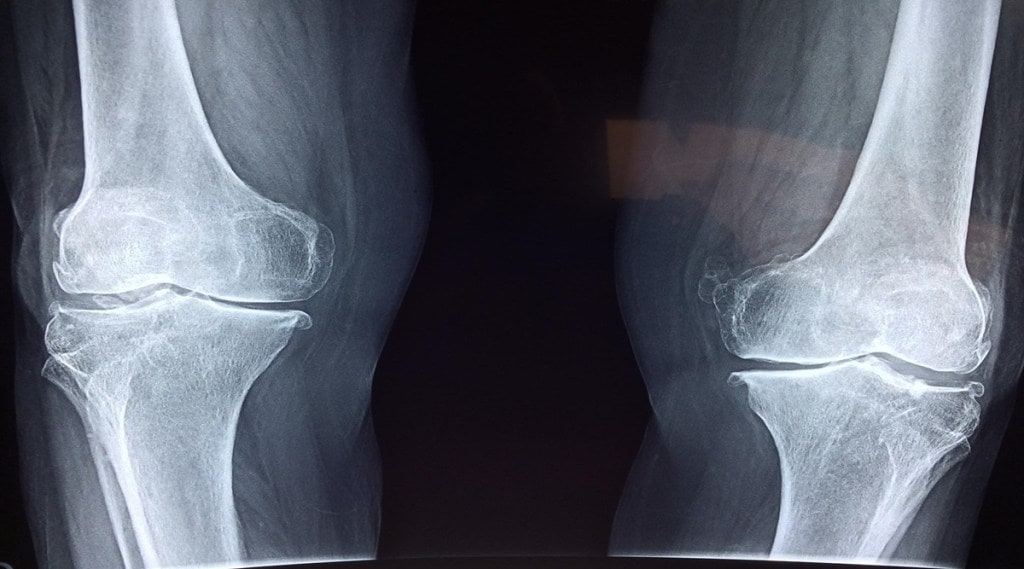

With the arrival of winters, people with injuries and arthritis complain of joint pains. Though there is no strong evidence suggesting a link between winter and joint pain, the possible cause may be the pressure that the air around us exerts on us decreases in the winter. This decrease in pressure has the potential to make the tissues near the joints expand and become more painful. The impact of heat can be used to explain the other potential wintertime cause of knee discomfort. During the winter, the fluid in tissues becomes more viscous. This increased viscosity causes the muscles’ suppleness to decline, which contributes to winter aches and pains.

- During the winter, the lubricant that protects our joints may thicken, which causes the joints to stiffen.

- Joint discomfort might originate from tissues expanding as a result of the drop in air pressure that comes with the arrival of cold weather.

- The winter months may cause the joints’ nerves to become more sensitive, which would exacerbate uneasiness.